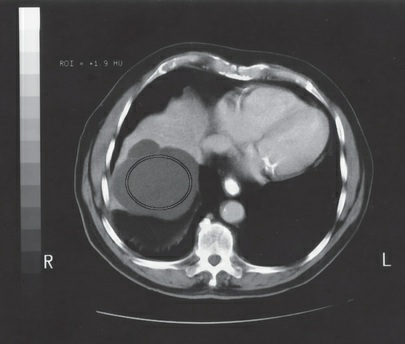

Which of the following components of CT image quality are

being evaluated in the figure?

1. low-contrast detectability

2. noise

3. uniformity

a. 2 only

b. 1 and 2 only

c. 1 and 3 only

d. 2 and 3 only

2 and 3 only

The differences in Hounsfield value exhibited in the regions of

interest (ROIs) measured on this CT image of a water-filled

phantom are most likely due to the phenomenon referred to as:

a. partial volume averaging

b. noise

c. beam hardening

d. detector drift

beam hardening

Which region of interest (ROI) on the figure demonstrates the

greatest amount of image noise?

a. 1

b. 2

c. 3

d. impossible to determine from the information provided

1

The region of interest (ROI) measurement in the figure

provides an average density of +1.9 HU. This material is most

likely:

a. fat

b. blood

c. tumor

d. water

water

The image in the figure was most likely displayed with the use

of which of the following window widths?

a. 70

b. 400

c. 1300

d. 3800

400